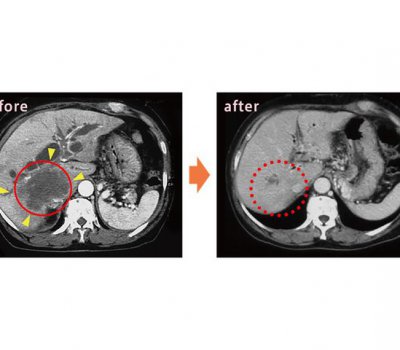

アルツハイマー型認知症を「治す・改善する」ことは難しくても、早い段階で診断できれば「進行をゆるやかにする」ことはできます。 2023年に新たに国内で保険承認されたアルツハイマー型認知症の点滴治療薬「レカ...